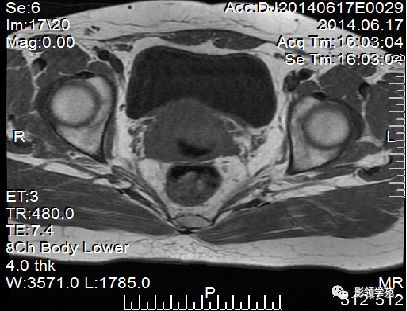

正常MR表现:卵巢和输卵管

卵巢:轴位和冠状面显示较佳,T1WI为中等或稍低信号,T2WI可因多个卵泡结构表现为高信号,但其间质部分仍呈稍低信号